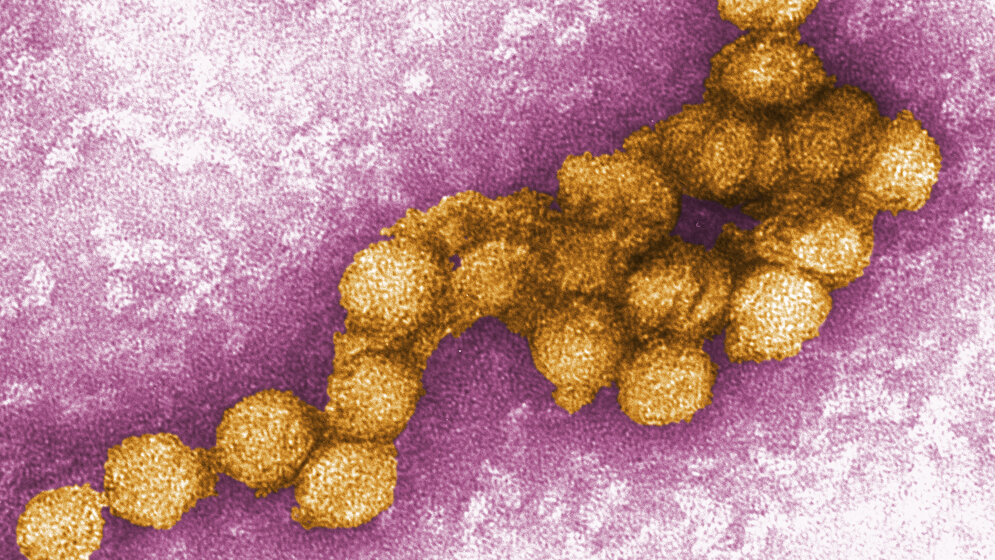

Laut Wellcome Trust werden die COVID-19-Kosten etwa 11 Billionen USD bis Ende 2021 betragen. Das Nicht-vorbereitet-sein kostet deutlich mehr als die Eindämmung von Infektionskrankheiten. Viele Ausbrüche schaffen es noch nicht einmal in die Nachrichtensendungen. Anbei finden Sie die „Top 10“ der vergangenen Jahre. Quelle: WHO/IHM data as of 12 January 2018